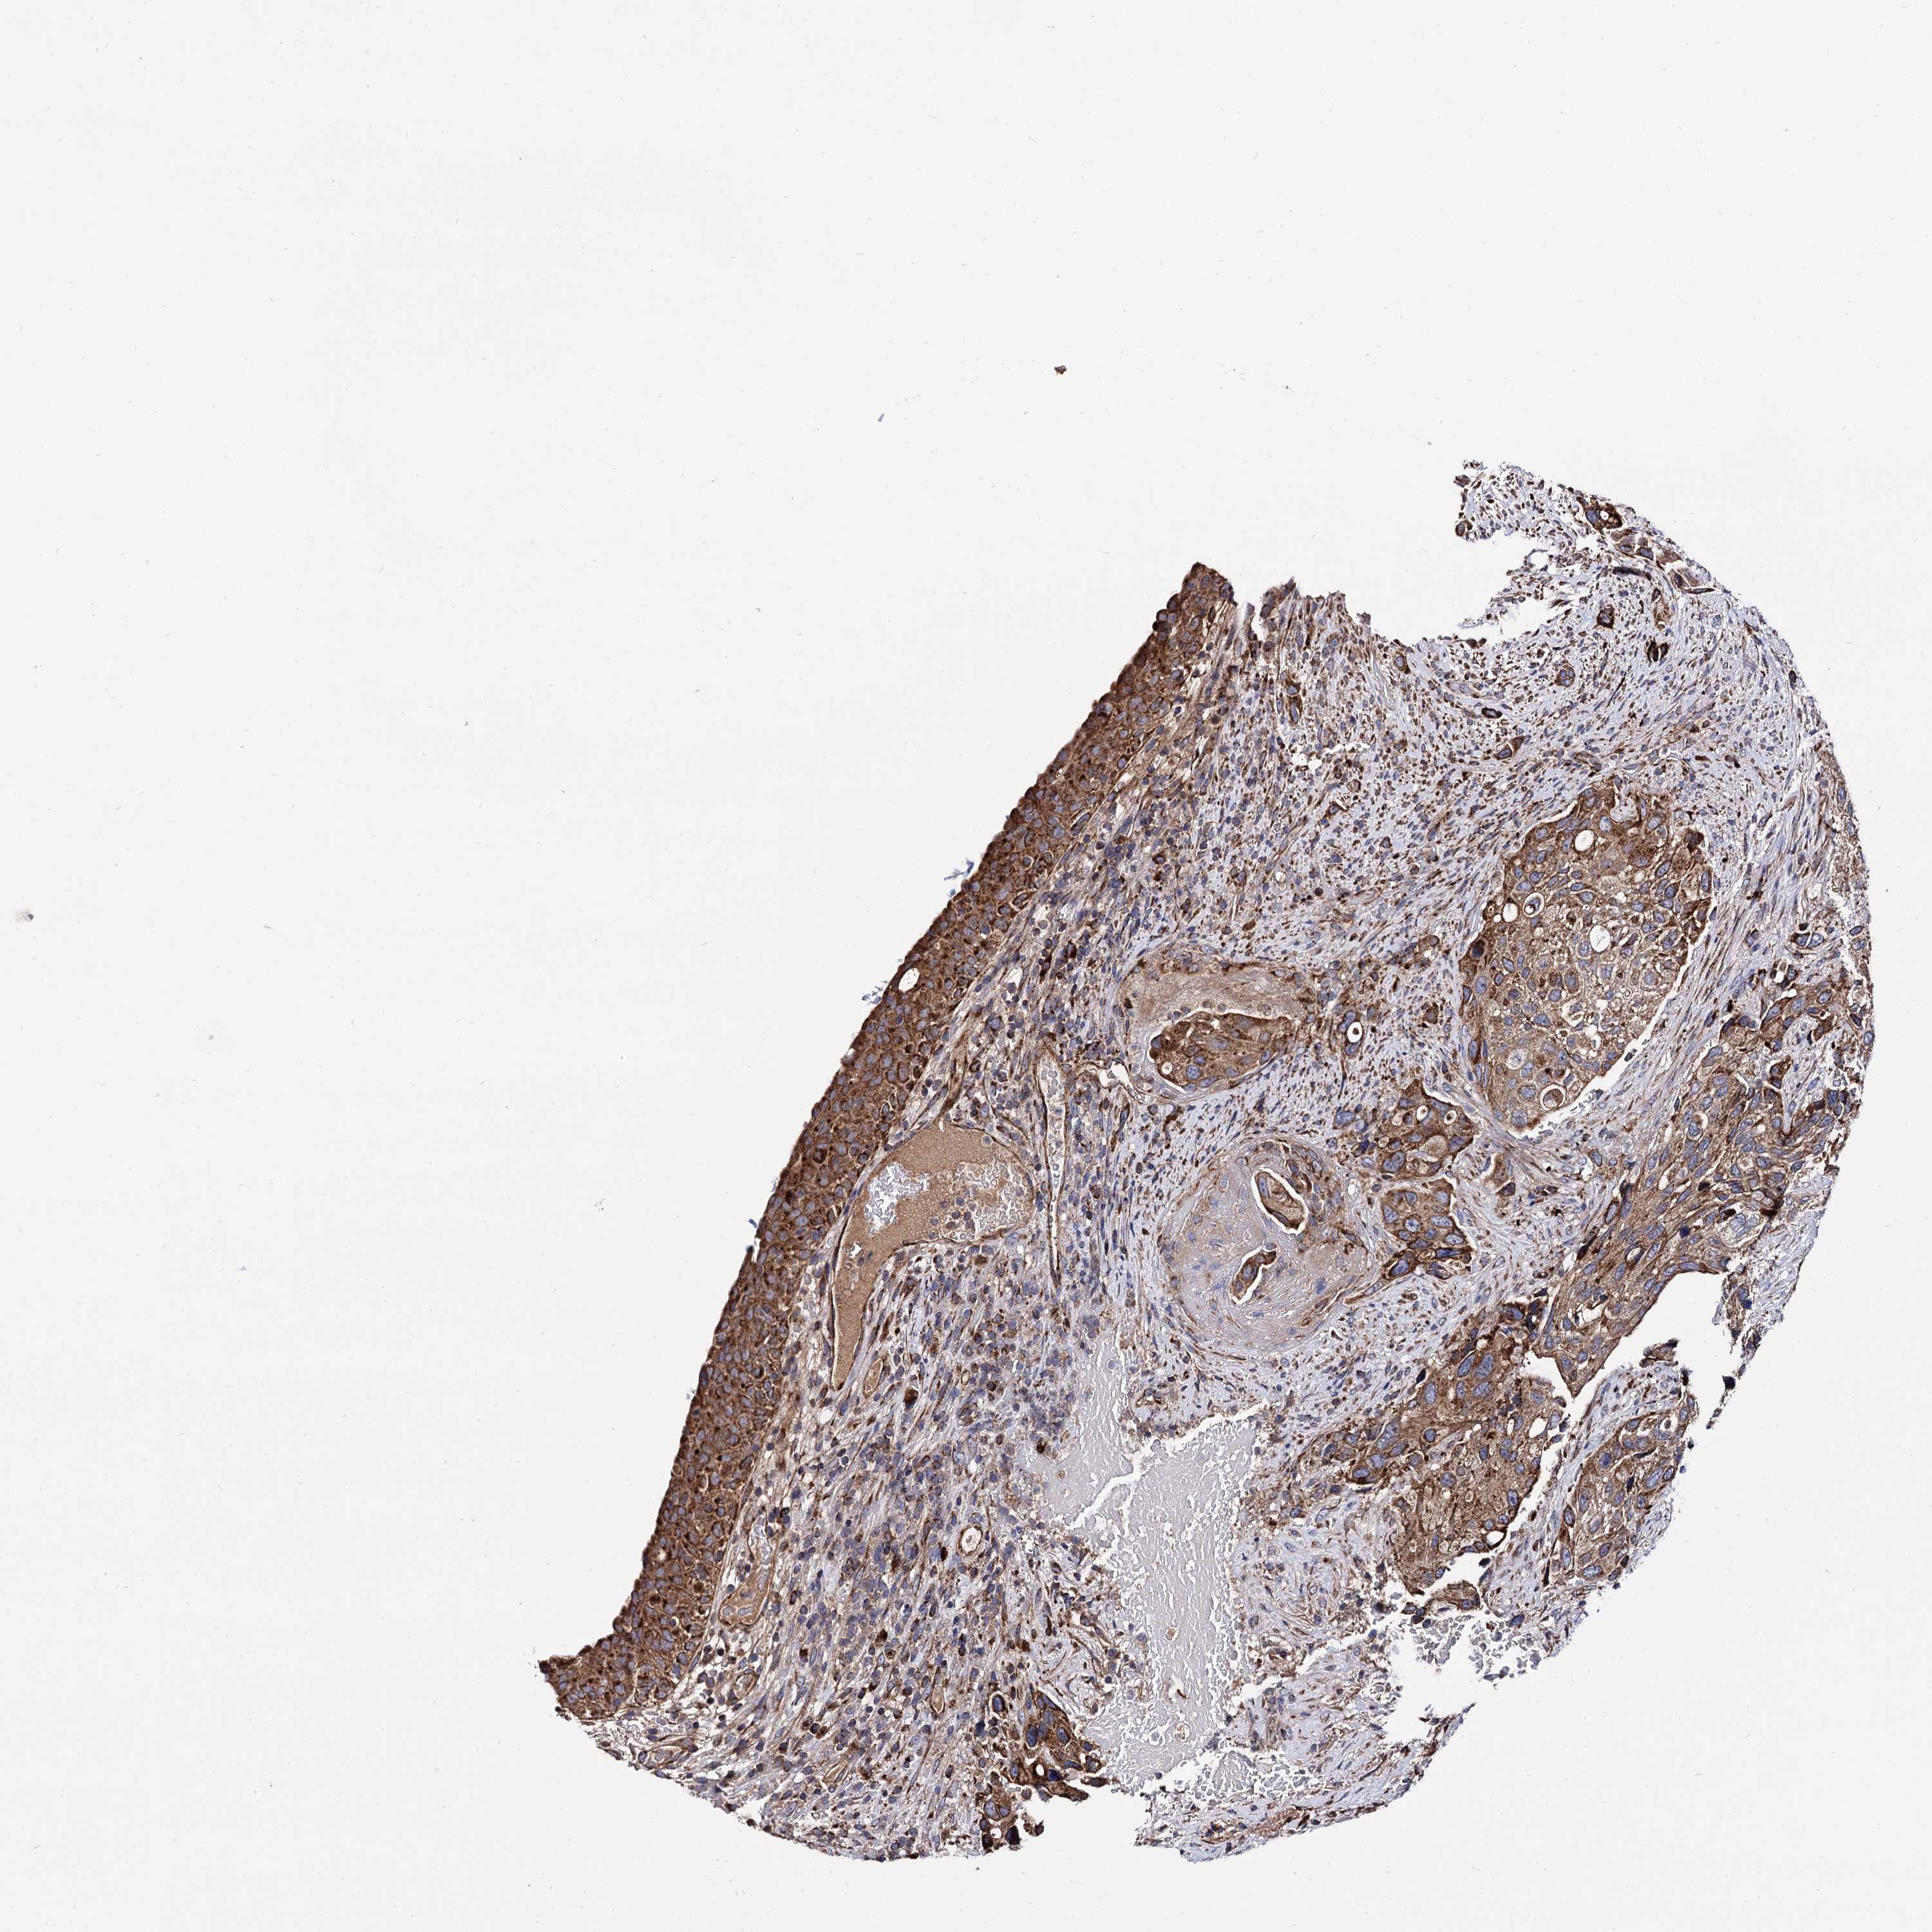

UROTHELIAL CANCER - Protein expressioni

A mouse-over function shows sample information and annotation data. Click on an image to view it in a full screen mode. Samples can be filtered based on level of antibody staining by selecting one or several of the following categories: high, medium, low and not detected. The assay and annotation is described here.

Note that samples used for immunohistochemistry by the Human Protein Atlas do not correspond to samples in the TCGA dataset.

Antibody stainingi

Antibody staining in the annotated cell types in the current human tissue is reported as not detected, low, medium, or high, based on conventional immunohistochemistry profiling in selected tissues. This score is based on the combination of the staining intensity and fraction of stained cells.

Each image is clickable and will lead to virtual microscopy that enables deeper exploration of all samples and also displays staining intensity scores, fraction scores and subcellular localization as well as patient and tissue information for each sample.

Antibody HPA040845

Staining

High

Medium

Low

Not detected

Intensity

Strong

Moderate

Weak

Negative

Quantity

>75%

75%-25%

<25%

None

Location

Nuclear

Cytoplasmic/membranous

Cytoplasmic/membranous,nuclear

Urothelial carcinoma, High grade